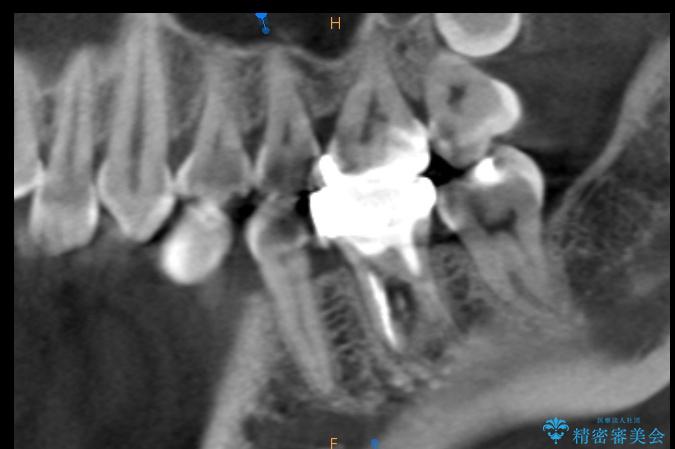

治療計画を立てる上で詳しく精密検査をしたところ、左下の6番目の歯につきまして治療が必要な状態であることが分かり、かぶせ物を外し、内部を確認しました。

結果としては深い部分で根が破折してしまっていました。

破折の処置としては基本的に抜歯が選ばれます。